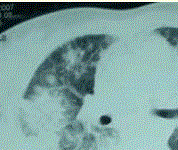

问题  患者女,23岁。间断发热伴皮疹1年半,诊断红斑狼疮。长期间断应用糖皮质激素治疗。近20 d来高热(T 39℃)伴咳嗽咳痰, CT(附图)示双肺满布圆形密度增高阴影,大小不等,密度不均匀,上、中肺野分布较多,双侧少量胸腔积液。血常规:WBC 2.52×10/L, N 0.62, Hb 92 g/L;ESR 40 mm/h; 痰真菌培养:烟曲霉3次阳性;支气管镜检查右下叶、左舌段见黄色黏液性血性分泌物,毛刷找到霉菌孢子。 如果要确诊本病例,临床上需要

选项 A、深部正常无菌组织培养发现曲霉生长或组织病理学检查发现曲霉菌丝 B、除外肺结核 C、除外肺部转移瘤 D、1,3-β-D-葡聚糖试验(G试验) 阳性 E、半乳甘露聚糖(galactomannan,GM)检测阳性

答案 A